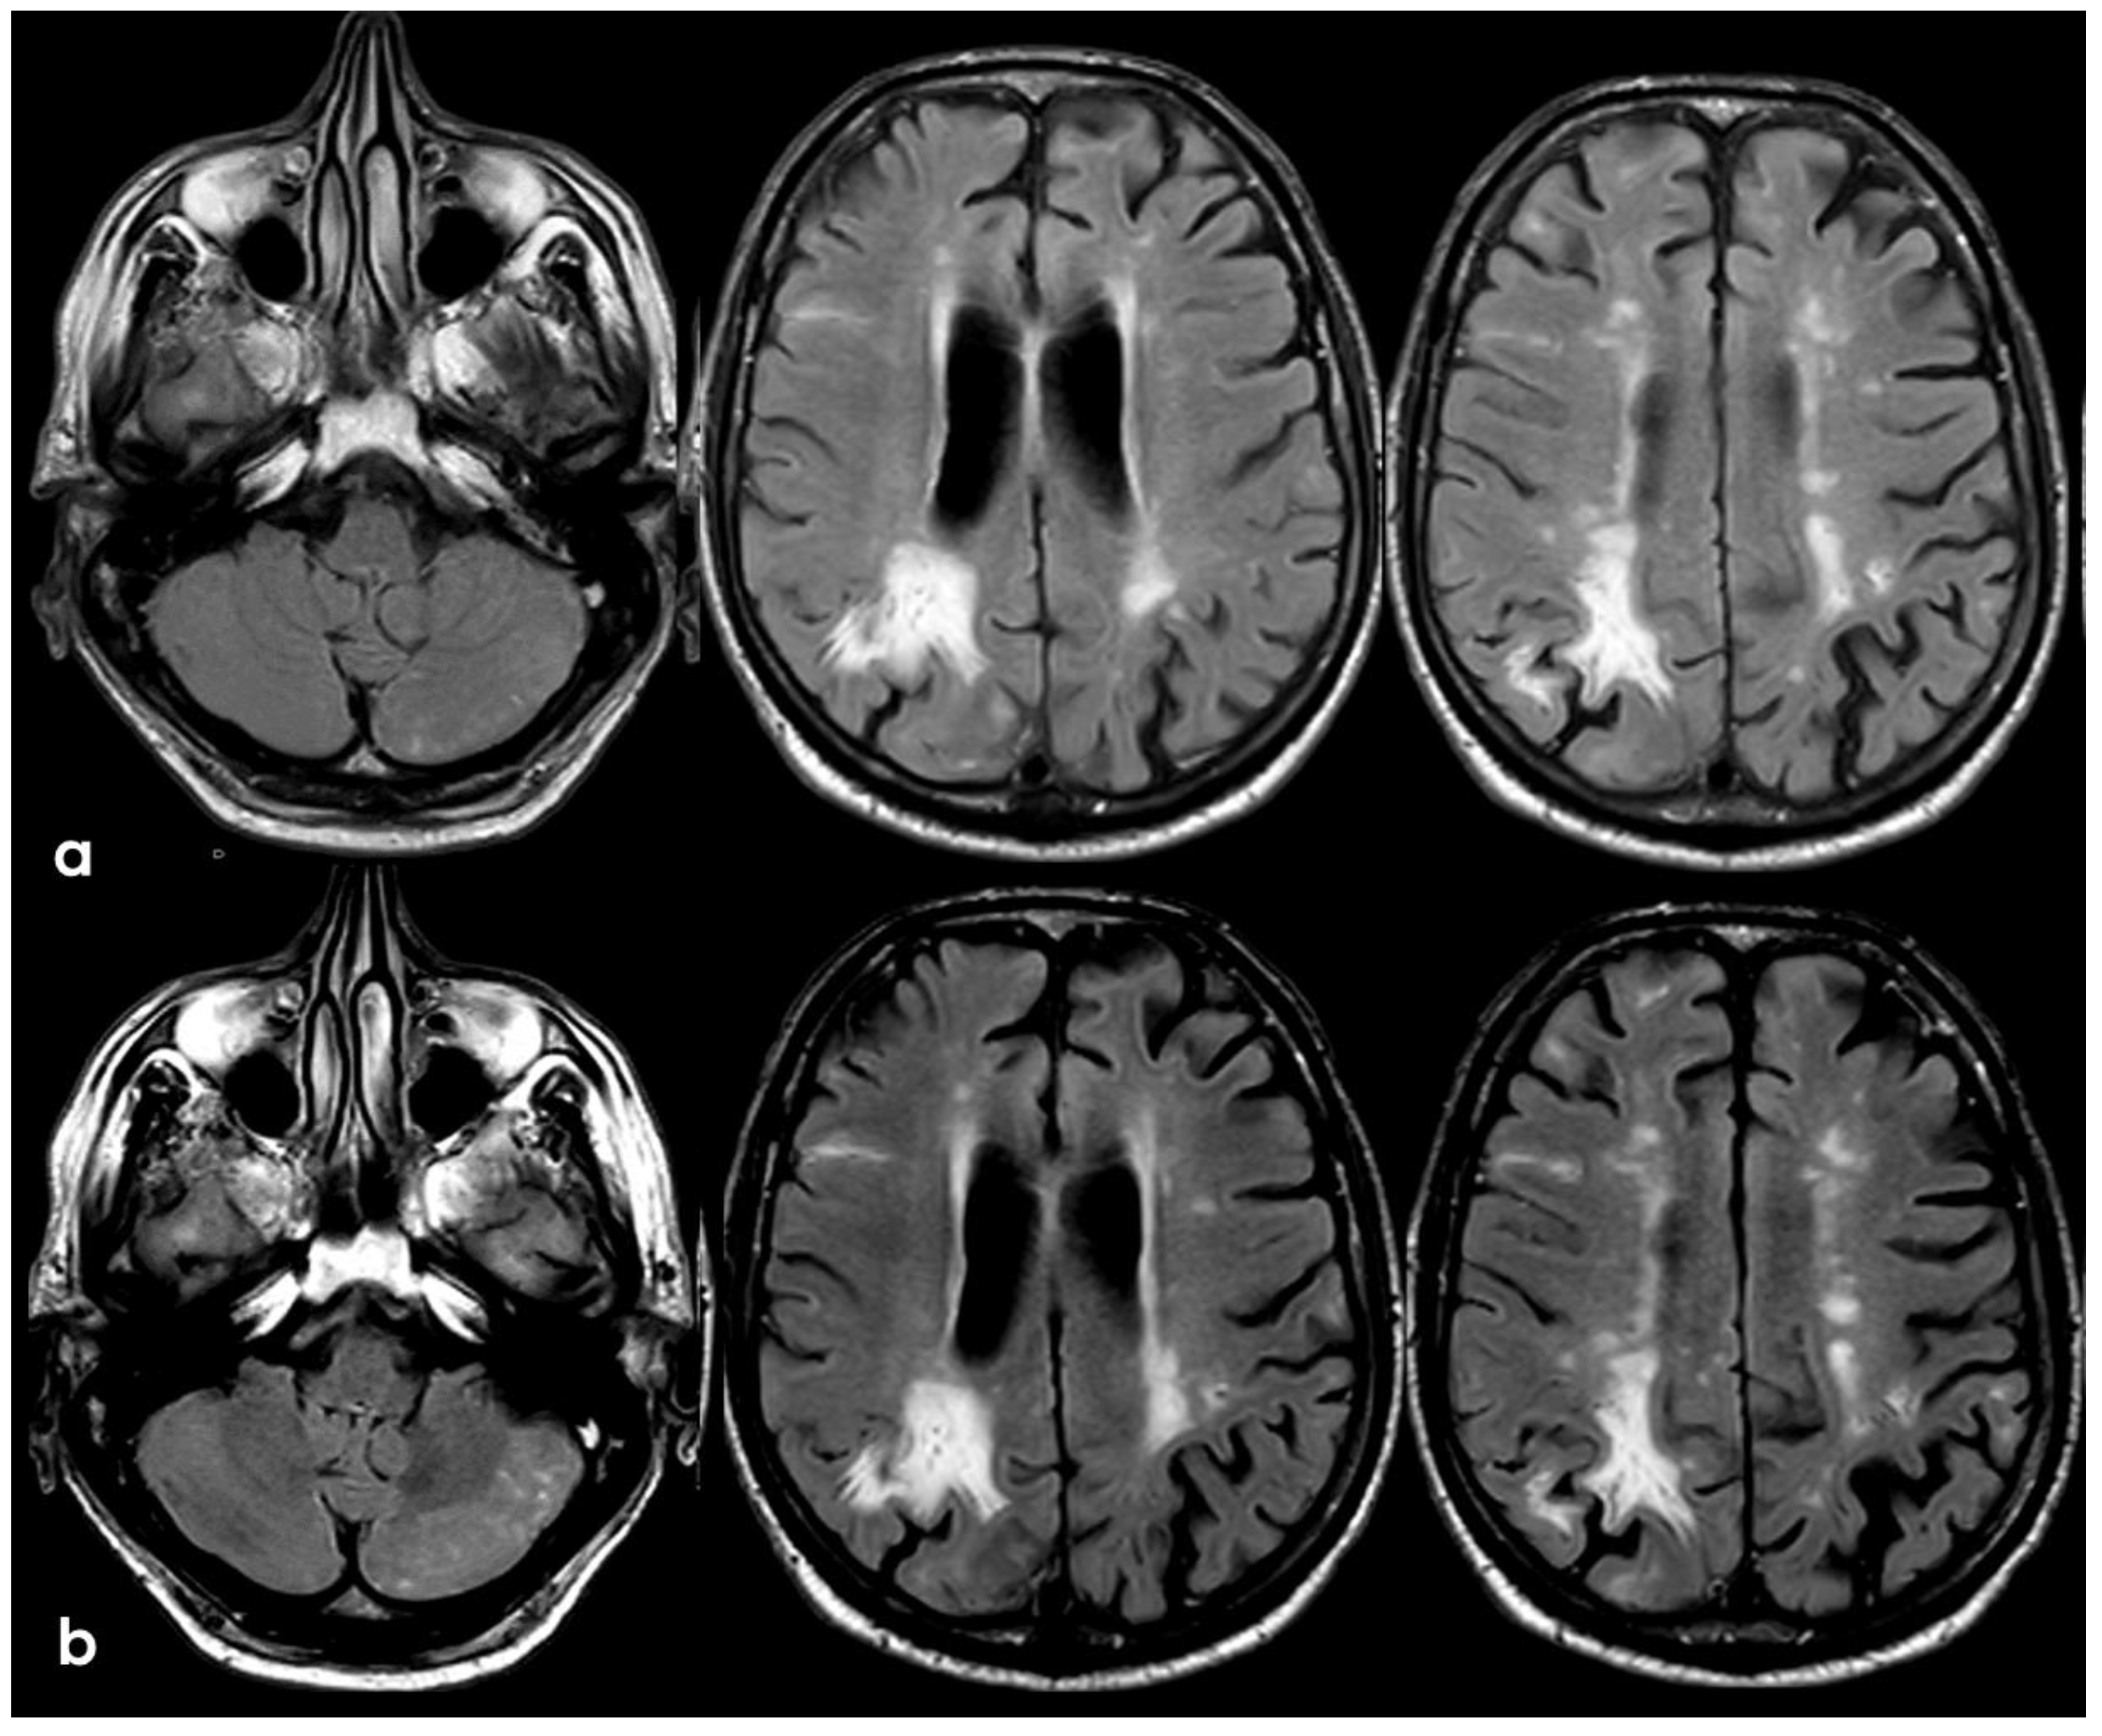

3. May 2014: CAA-Related Inflammation